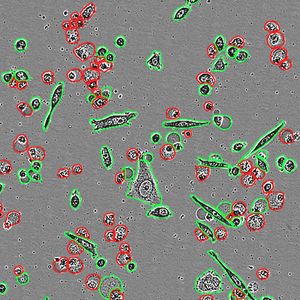

AUG 15, 2017CancerTo creep into distant parts of the body, some cancer cells have developed a knack for shapeshifting – morphing on ...